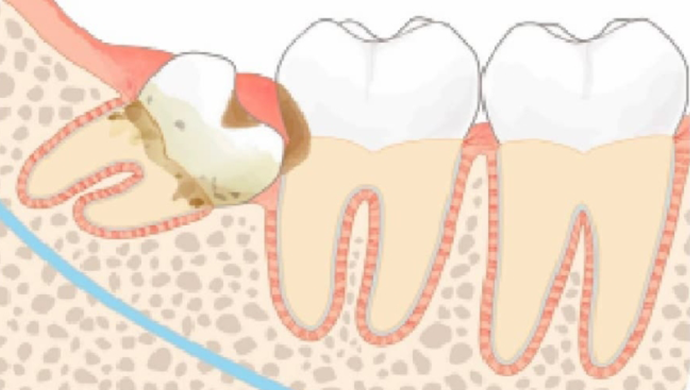

親知らずは第3大臼歯のことで、6歳臼歯の二本奥、前歯の中央から8本目の歯の事です。顎の骨が十分発達していると、親知らずは正常に生えて、きちんと食物を噛むことができます(必要な親知らず)。昔の人は顎がガッシリしており、親知らずが真っ直ぐに生えることが多かったようです。

しかし現代人では小顔のため、、親知らずがきちんと生えず、場合によっては骨の中に埋まってしまう場合が非常に多いのです。この「骨に埋まった親知らず」は、さまざまな問題を引き起こすことがあります。また、生えていても横をむいている親知らずは、物が詰まりやすく、その歯があるために周りの必要な歯まで虫歯にしてしまいます。また、噛み合う相手のいない親知らずは、噛む相手を求めて伸びてくるため、噛み合わせのズレを引き起こします。

親知らずは、斜めに生えていたり、半分埋まっていたりすることが多く、清掃性が悪いのが特徴です。その分、汚れが溜まりやすく、清潔に保つことが難しいため、一度虫歯や歯周病にかかってしまうと、完治させることが困難となります。時間をかけて治療しても、すぐまた再発してしまうのが親知らずであり、そればならば最初に抜歯を選択した方が、患者さまのメリットを最大化させることができるのです。